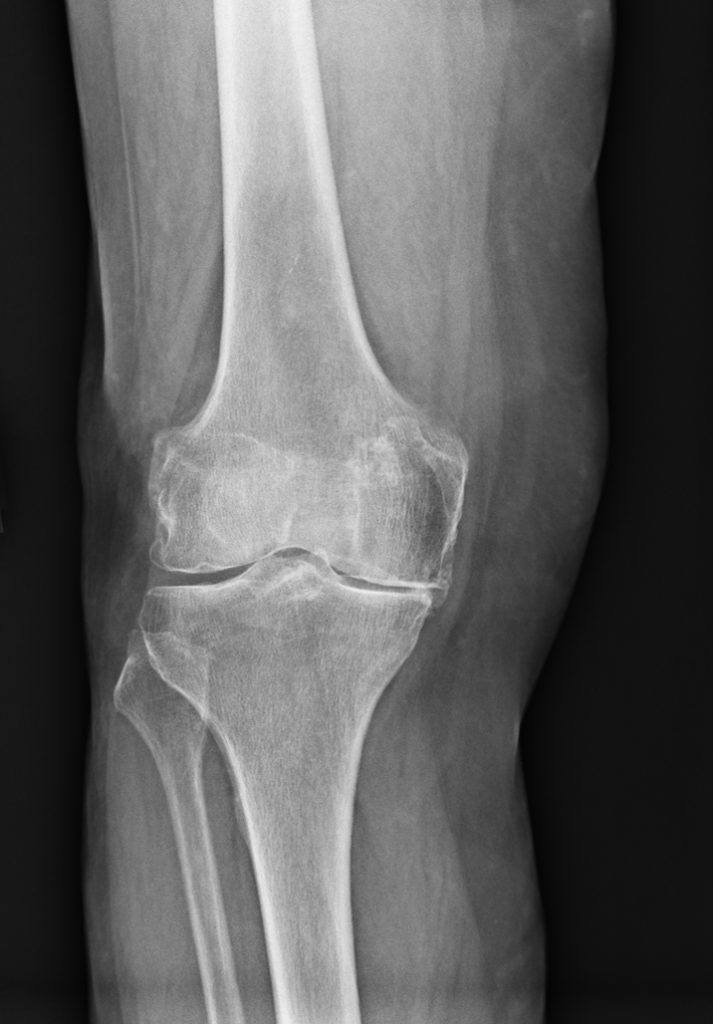

Rheumatoid arthritis in knees Stock Image M110/0193 Science Photo Library Arthritis Flare Up In Knee Although there is no cure for knee arthritis, there are. What causes them and exactly what to do when you have one. arthritis of the knee can be a serious, debilitating disease. A flare is a period of increased disease. Some medications, lifestyle changes, and home. when your arthritis symptoms suddenly crank up to 11 out of 10,. Arthritis Flare Up In Knee.

Xray Stages of Knee Arthritis YouTube Arthritis Flare Up In Knee Some medications, lifestyle changes, and home. A flare is a period of increased disease. Although there is no cure for knee arthritis, there are. This unexpected increase in your disease. when your arthritis symptoms suddenly crank up to 11 out of 10, you know that you are experiencing a flare. What causes them and exactly what to do when. Arthritis Flare Up In Knee.